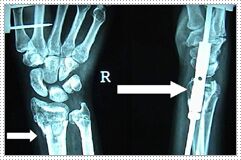

X-Rays of the forearm and wrist are taken.

You will be given medication to lessen the pain. If necessary, your doctor are will move the ends of the broken bones back into proper alignment. If the break is very severe, you may be given general anesthesia so that the bone can be repositioned during surgery. A cast or splint may be applied to help maintain the position of the bones. To maintain the alignment an external fixator may be applied as shown below. X-Ray on the left shows fracture and the pins. The arrow in the right side X-Ray shows the rod of the external fixator. In some cases small wires are passed under anaesthesia to maintain aligmment. Wires as well as external fiaxtor needs no cutting of the skin and can be taken out without anaesthesia in the Out patient Department. A Colles’ fracture usually takes up to 8 weeks to heal. X-Rays may be taken from time to time during recovery to see how it is healing. When the cast or splint is removed, the affected wrist and the fingers, hand, and shoulder on that side may be stiff for several more weeks. Your health care provider may prescribe exercise and physical therapy. You will not be able to bend your wrist while the cast or splint is in place. You may need someone to help you with daily activities such as cooking, housework, driving, and self-care (showering and dressing) until the cast or splint is removed. Older people in poor health may need extra help to maintain an independent lifestyle while they recover from a Colles’ fracture.